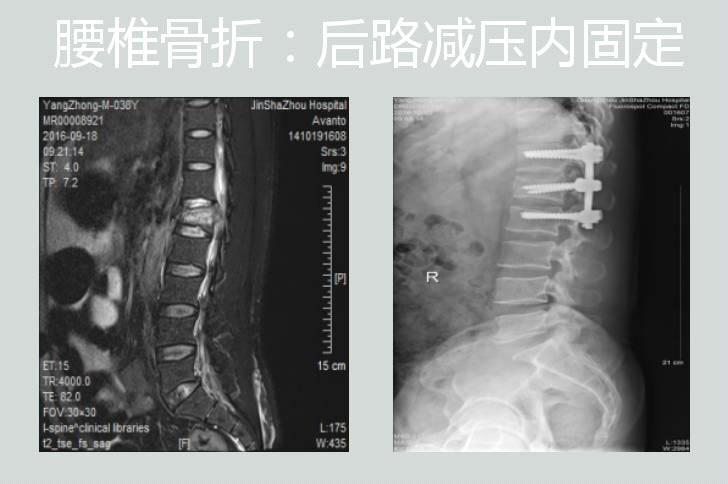

后路椎弓根螺钉内固定复位植骨融合治疗腰椎滑脱症或椎体爆裂性压缩性骨折;